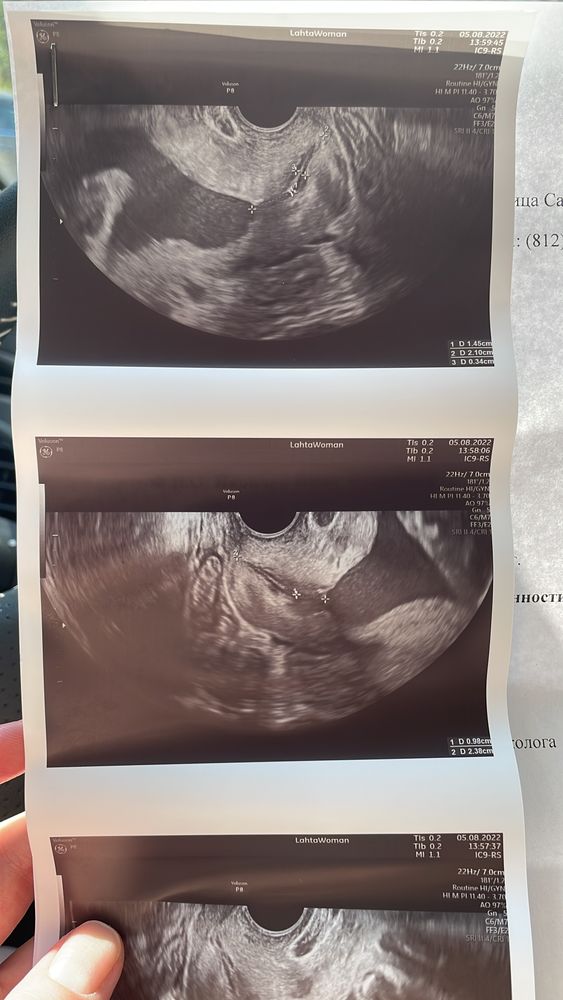

Девочки. SOS. Цервикометрия

УЗИ, КТГ, доплер(Фото внутри) Посмотрите, пожалуйста!

мониторю шейку, сегодня срок 29+1. Длина шейки 36мм, хорошая, но появилось воронкообразное расширение. Написала гине, жду ответа от неё. Успокойте, скажите, что это норма!! Не рано ли шейка сглаживаться начала?

upd: повтор цервикометрии через неделю. Все хорошо. Врач просто попалась неумная мягко говоря